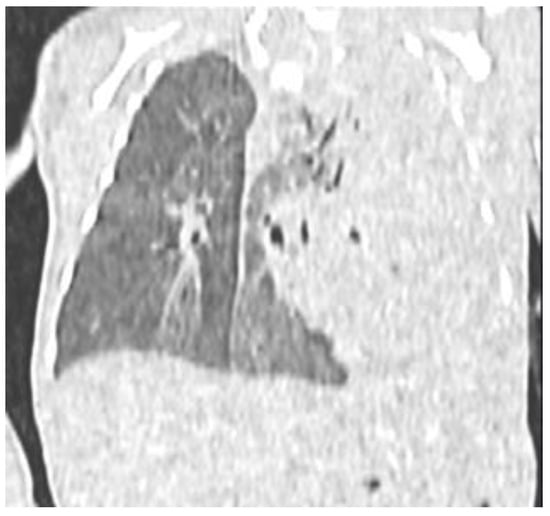

2. Case Presentation